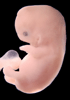

Carnegie Stage 19 (47 post-ovulatory days)

About Carnegie Stage 19

Most embryos at stage 19 are approximately 47-48 post-ovulatory days old and measure 17-20 mm in length. Distinguishing criteria for this stage include straightening of the trunk, the limbs extend nearly directly forward, toe rays are prominent, but interdigital notches have not yet appeared in the foot.

Although some of the photographs below show abnormal embryos, the animations and MRI slice images all depict normal embryos. Abnormal embryos are noted in the titles of the large photos when they are opened.